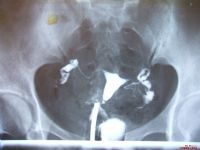

1.B超連續檢測。於圍排卵期第8~9天起。每日用陰道B超連續觀察了解卵泡發育動態情況,若有優勢卵泡形成,達成熟卵泡標準(卵泡最大直徑>18mm晰透亮、邊界清楚等),而無排卵表現,即卵泡持續不消失或無明顯縮小(卵泡滯留型),或繼續增大(30~45mm,卵泡持續長大型),子宮直腸陷凹無游離液出現,即可考慮為未破裂卵泡黃素化(LUF)周期。在B超監測周期中,應由專人專機檢查,以統一標準,避受將排卵後的囊性黃體誤認為LUF。

2.腹腔鏡檢查。對疑有未破裂卵泡黃素化時,行腹腔鏡檢查可進一步確診。一般認為在排卵後1.5天內排卵征依然存在,此後會逐漸封閉,於4~5天完全上皮化,排卵孔封閉。故於黃體早期(月經周期第20天前,BBT上升2~4天)用腹腔鏡直接觀察卵巢面,見有黃體但無排卵裂孔。